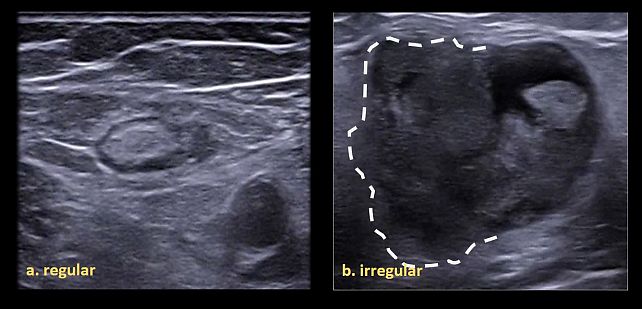

- Shape: described as regular (oval/elliptical or round) or irregular (lobulated or with spicules on the outer margin) (Figure 3).

3

Classification of lymph node shape as regular (a) or irregular (b).